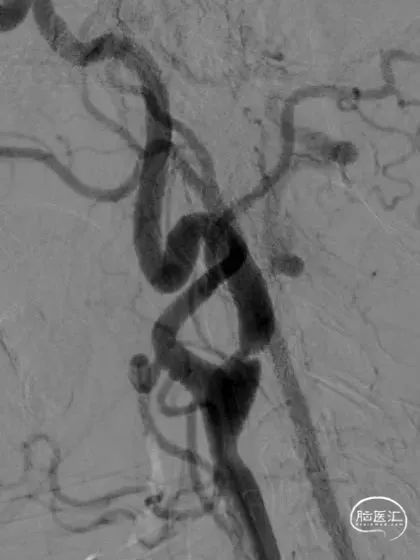

右侧颈内动脉起始段重度狭窄

左侧颈内动脉起始段重度狭窄

左侧颈内动脉颅内段充盈明显延迟